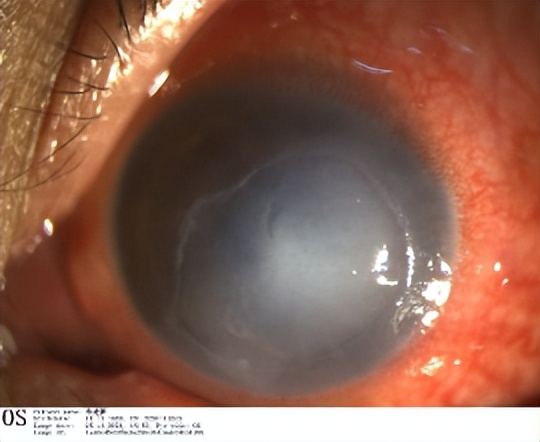

现病史:患者因左眼红伴视力下降1月余,加重14天入院,2月前行三叉神经瘤手术

检查:

Vos:HM/眼前,角膜可见5*7mm上皮缺损,基质混浊,角膜知觉明显减退

共聚焦显微镜:中央区角膜基质神经纤维缺失,周边区明显减少

入院诊断:左眼神经营养性角膜炎,三叉神经瘤术后